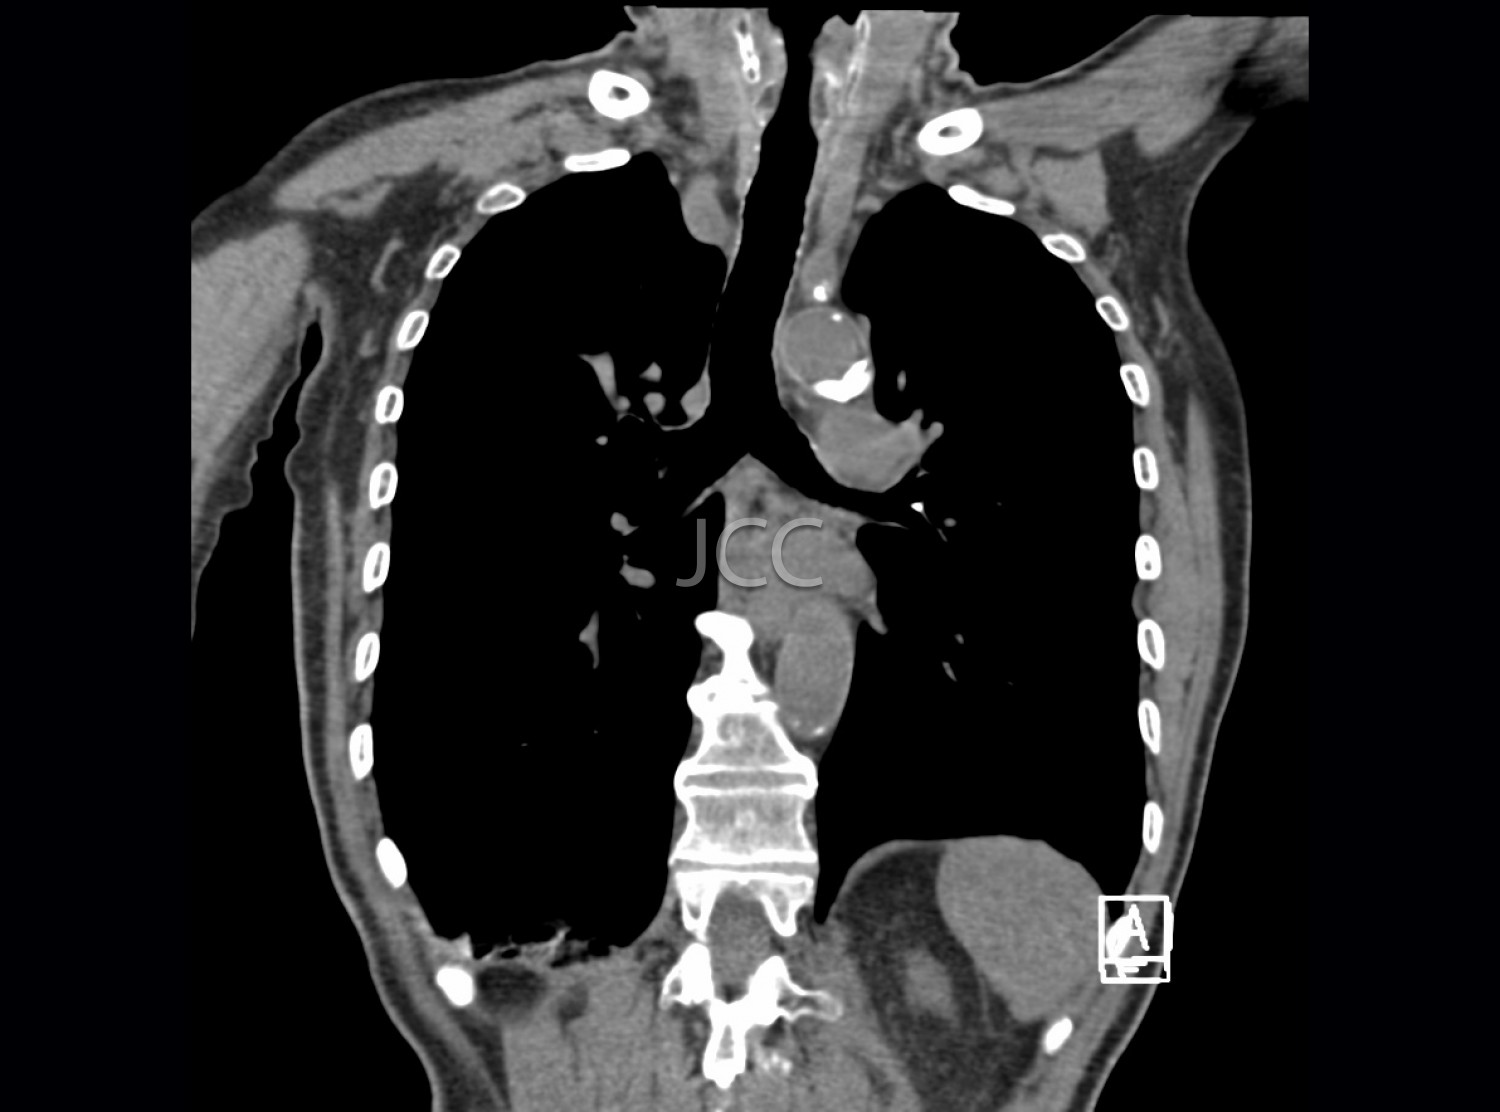

Computed Axial Tomography - Thoracic

Computed Axial Tomography (CAT) - Dual Energy - 256 slices is a diagnostic technique that allows the evaluation of various parts of the human body, including the lungs, liver, pancreas, kidneys, heart, vascular structures and bone structures.